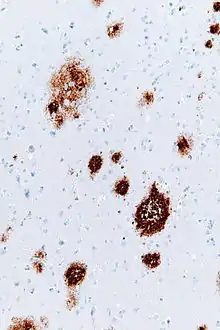

Amyloid beta immunostaining showing amyloid plaques (brown)

Amyloid plaques are visible with the light microscope using a variety of staining techniques, including silver stains, Congo red, Thioflavin, cresyl violet, PAS-reaction, and luminescent conjugated oligothiophenes (LCOs).[32][4][33] These methods often stain different components of the plaques, and they vary in their sensitivity[4][34] Plaques may also be visualized immunohistochemically with antibodies directed against Aβ or other components of the lesions. Immunohistochemical stains are especially useful because they are both sensitive and specific for antigens that are associated with plaques.